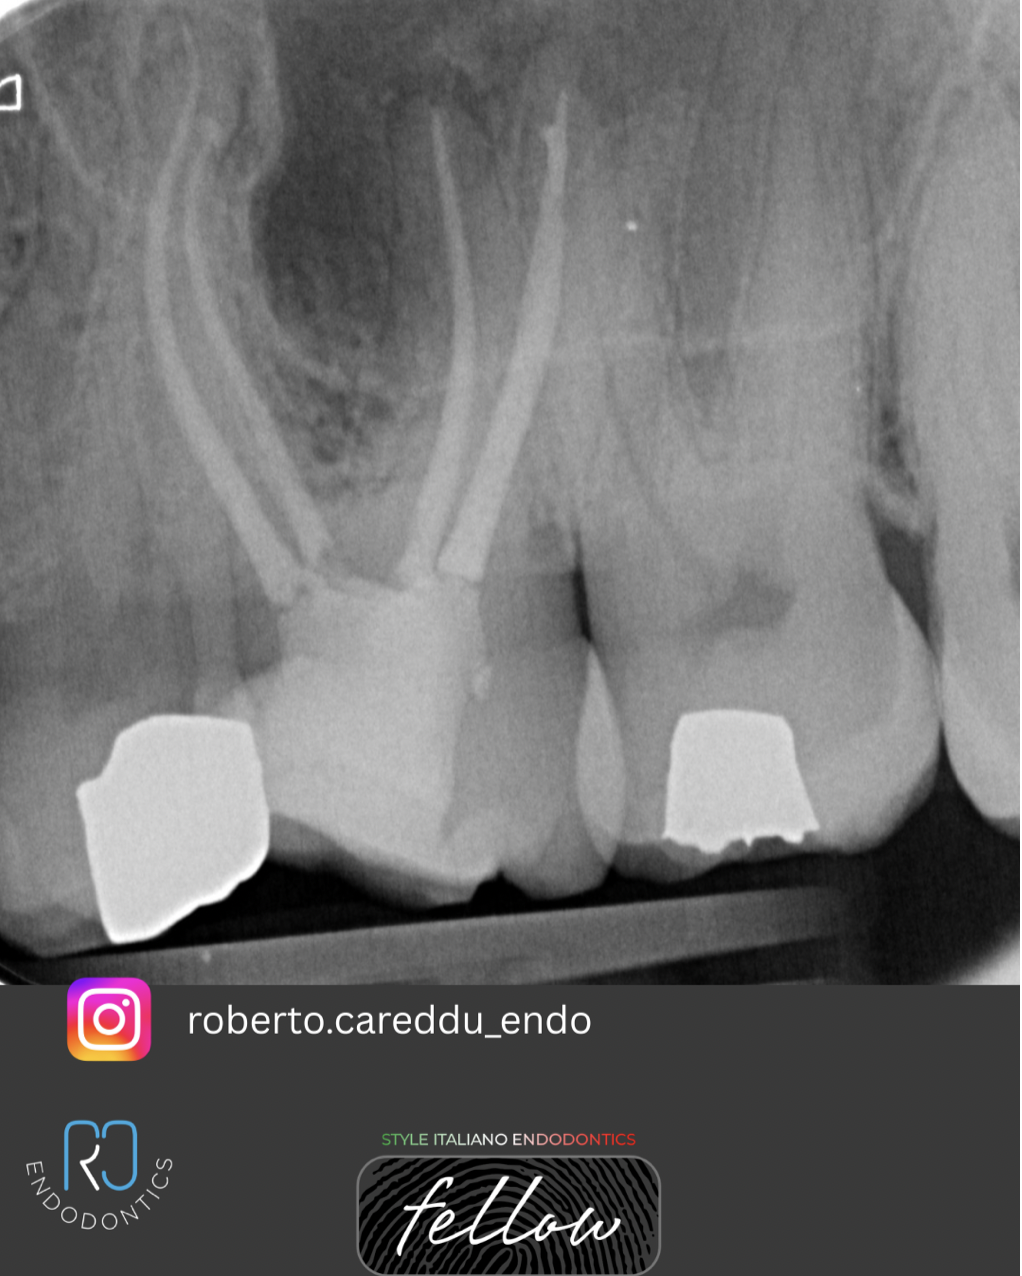

Fig. 2

The existing amalgam restoration was removed, and access to the pulp chamber was established. The material was then carefully removed using ultrasonic tips and austenitic rotary files. The canal system was shaped and irrigated with sodium hypochlorite (NaOCl) and EDTA, with sonic activation to enhance effectiveness. The canals were subsequently obturated using a hydraulic cement in combination with gutta-percha.

Fig. 3

Once the canal system was sealed, a permanent fibre reinforced resin filling was placed